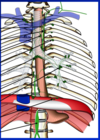

(8) Cardio Angiology (Olinger) Flashcards

(49 cards)

Label:

Label:

Label:

Label:

Label

Label:

Label:

Label:

Label:

Label: